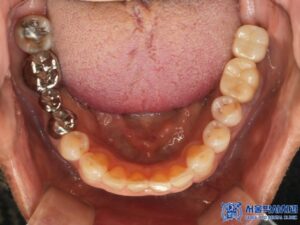

오늘은 오래전에 하악 어금니를 발치하고

그 상태로 지내시다가,

전체적으로 치료를 받으러 오신 환자분의

임플란트 치료 및 신경 치료 사례를

소개해 드리도록 하겠습니다.

환자분은 좌측 아래쪽 어금니가 없는 상태였고,

오랫동안 방치되어 치조골(잇몸뼈)의

변화가 일부 있었습니다.

하지만 다행히도 임플란트를 식립하기에

충분한 골량이 유지되고 있었고,

무절개 방식으로 빠르게

임플란트를 진행할 수 있었습니다.